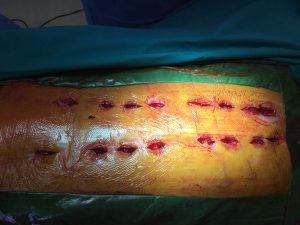

Η χειρουργική επέμβαση πραγματοποιήθηκε τον Δεκέμβριο. Η σταθεροποίηση της Θωρακικής Μοίρας της Σπονδυλικής Στήλης (Θ.Μ.Σ.Σ.) δια της διαδερμικής εφαρμογής συστήματος σπονδυλοδεσίας, κατόπιν οπισθίας προσπελάσεως.

Η χειρουργική επέμβαση έγινε υπό συνεχή νευροπαρακολούθηση και η διαδερμική τοποθέτηση των κοχλιών στους σπονδύλους έγινε με το σύστημα πλοήγησης O-ARM.

- δ

Εικόνα 3 Διεγχειρητικές φωτογραφίες .Τοποθέτηση των κοχλιών στα σπονδυλικά σώματα: Οι κοχλίες είναι ειδικοί αυλοφόροι που παρέχουν τη δυνατότητα να εγχέεται methylmethacrylate (ακρυλικό τσιμέντο) μέσα στα σπονδυλικά σώματα, για ασφαλέστερη συγκρότηση των κοχλίων. Οι ράβδοι τοποθετούνται επίσης διαδερμικά.

-3. Η σταθεροποίηση του κατάγματος της Θωρακικής Μοίρας της Σπονδυλικής Στήλης (Θ.Μ.Σ.Σ), πραγματοποιήθηκε με την εφαρμογή συστήματος σπονδυλοδεσίας, το οποίο τοποθετήθηκε διαδερμικά. Με την τεχνική αυτή περιορίζονται σημαντικά οι κακώσεις των μαλακών μορίων και οι απώλειες αίματος, γεγονός που σημαίνει οτι η κινητοποίηση του χειρουργημένου είναι πολύ γρήγορη.

Δεδομένου ότι οι κοχλίες τοποθετούνται μέσα στα σπονδυλικά σώματα, υπό την καθοδήγηση του ειδικού ακτινολογικού συστήματος πλοήγησης O-ARM εξασφαλίζεται η, με μεγίστη ασφάλεια, είσοδος των κοχλίων σε περιοχές εξαιρετικά επικίνδυνες λόγω της ύπαρξης νευρικών και αγγειακών στοιχείων (8).

Δια της εφαρμοζόμενης διαδερμικής τεχνικής στη τοποθέτηση των υλικών σπονδυλοδεσίας επίσης περιορίζονται σημαντικότατα οι κίνδυνοι να προκληθούν νεκρώσεις του δέρματος και λοιμώξεις, λόγω των προηγηθεισών ακτινοβολιών στη περιοχή αυτή της Σπονδυλικής Στήλης.